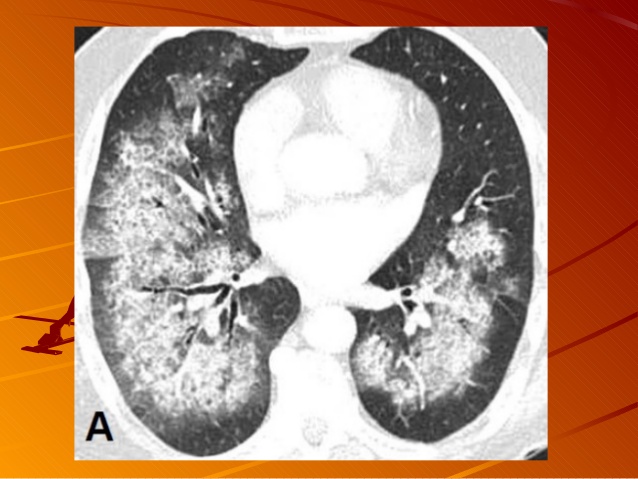

Chụp X-quang, chụp cắt lớp CT Scan ngực.